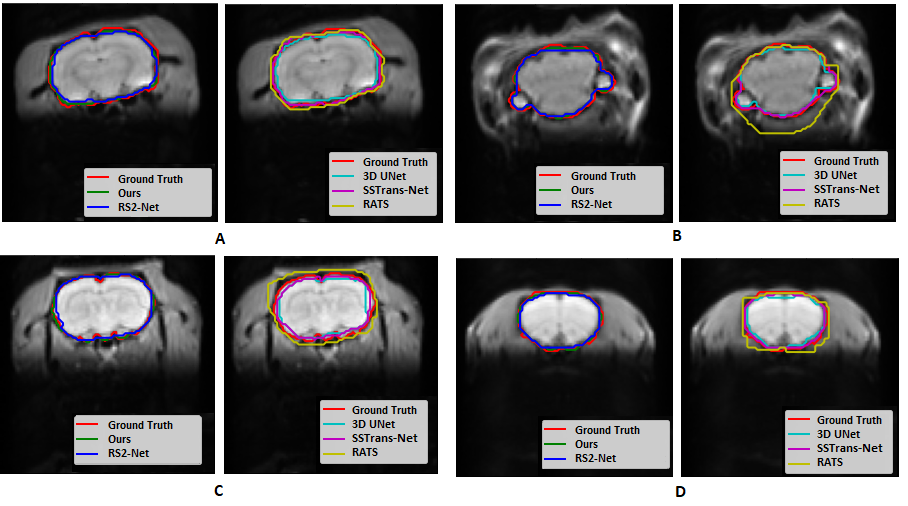

Refer to caption

Figure 4: This figure presents the skull-stripping results across various CTNI datasets (A, B: dataset 1- C: dataset 2, D: dataset 3). The red region indicates the manually annotated ground truth, while the areas outlined in different colors correspond to the results produced by different methods.

To evaluate the performance of our proposed method, skull stripping results from two subjects in the dataset 1 test set are presented in Figure 4A and B, showing slices from both the middle and back regions of the brain. Additionally, results from a single slice of one subject from dataset 2 and dataset 3 are illustrated in Figure 4C and D. As shown in Figure 4, RATS tends to misclassify non-brain tissues as brain, whereas all deep learning-based methods effectively extract brain tissues. Further comparisons of deep learning-based methods applied to two fMRI samples from dataset 1 are visualized in Figure 5, offering three different views for a more comprehensive assessment.

The Dice metrics for each slice, reported in Table 3, provide a quantitative comparison of the methods. These results highlight that our proposed method outperforms existing techniques and offers a reliable solution for preclinical skull stripping.

Table 3: Dice metric values related to Figure 4 and Figure 5, samples A and B are from dataset 1, sample C, and sample D belongs to dataset 2, and 3 respectively.

Figure 4

Method Sample A Sample B Sample C Sample D

RATS 0.9012 0.8756 0.8667 0.8979

3D UNet 0.9536 0.9427 0.9384 0.9415

SSTrans-Net 0.9712 0.9678 0.9542 0.9654

RS2-Net 0.9751 0.9697 0.9567 0.9686

SST-DUNet(ours) 0.9819 0.9781 0.9687 0.9773